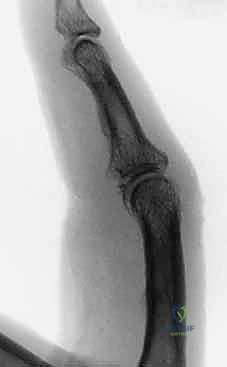

الحالة الأولى: كسر خلع ظهري مفتت بشدة

- قبل الجراحة: تظهر الأشعة خلعاً تاماً للمفصل مع تفتت شديد في قاعدة السلامية الوسطى.